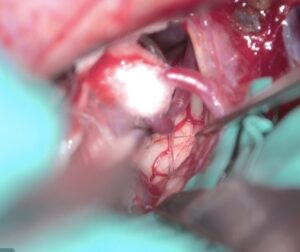

左三叉神経痛の手術をしました。カルバマゼピンで抑えられい強い痛みがありましたが、手術後痛みが完全になくなり食事も取れるようになりました。 2025 12/05 顔面痙攣・三叉神経痛 2025年12月5日ScreenshotScreenshotScreenshotScreenshotScreenshot 顔面痙攣・三叉神経痛 よかったらシェアしてね! URLをコピーしました! URLをコピーしました! 2025/9月 左聴神経腫瘍の手術をしました。術後顔面神経麻痺が出現しましたが2ヶ月程度で回復しました。 250910 西嶋久勝 高浜新町長にお会いしました。 この記事を書いた人 kikuta 関連記事 2603月 67歳男性の右顔面痙攣を手術しました。 2026年3月22日 2603月 58歳女性の左顔面痙攣を治療しました。VAとAICAの複合型圧迫でしたがうまく治癒できました。 2026年3月21日 46歳男性、開眼できないほどのVA型左顔面痙攣を手術しました。術後まだ完全には消失していませんが痙攣は著明に軽減しました。 2026年3月3日 19歳女性の三叉神経痛を手術しました。術後痛みは消失した様子です。 2026年3月3日 87歳女性、繰り返しブロックを行いガンマナイフも行った、難治生三叉神経痛を手術しました。高齢ですが無事一発治癒しました。 2025年12月11日 2025年8月 78歳 VA型の顔面痙攣の神経減圧術を行いました。M-TEPを併用し無事治癒しました 2025年12月4日 2025年5月 テグレトールで治らない左三叉神経痛の手術を行い直後より痛みは消失しました。 2025年9月25日 畑山式MVDハンズオンセミナーに東野先生と参加してきました 2025年3月22日